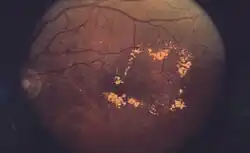

| A 61-year-old man with medical history of type 2 diabetes that presents a macular edema, evidenced by an OCT (the edema marked with arrows). The central image is a 3D reconstruction of the retinal thickness (the edema is coloured in red). | |